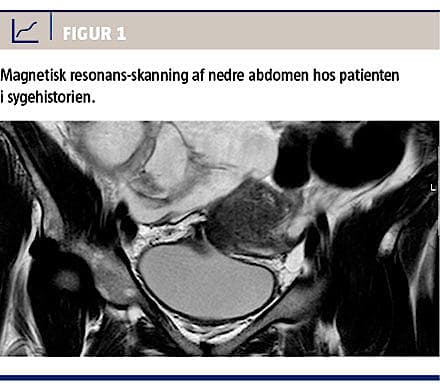

På en urologisk afdeling behandlede man en 32-årig kvinde med dette syndrom. Fire måneder efter at have fået foretaget et kejsersnit, blev hun henvist til et sygehus pga. hæmaturi og urin per vaginam. Primær mistanke var en vesikovaginal fistel. Dette blev bekræftet ved installation af methylenblåt i blæren, hvorefter man så blå farve i fornix posterior. Senere undersøgelser med CT-urografi og -cystografi bekræftede ikke denne diagnose. Knap et år efter kejsersnit blev hun henvist til OUH til videre udredning og behandling. Man havde endnu ikke visualiseret en fistel, og patienten var nu meget påvirket af symptomerne i sin hverdag med urinafgang per vaginam og makroskopisk hæmaturi under menstruation. Ved cystoskopi og magnetisk resonans-(MR)-skanning (Figur 1) blev der fundet en fistel mellem vesica og uterus. Fistlen i blæren blev excideret, og uterus blev fjernet efter patientens ønske. Hun blev udskrevet i velbefindende.

Hvis man har mistanke om, at patienten har en vesikouterin fistel, bør hun henvises til en højtspecialiseret afdeling. Hvis CT-urografi og eventuelt andre undersøgelser (cystoskopi og ultralydskanning) har vist normale forhold, bør patienten henvises til en MR-skanning af nedre abdomen [5]. I maks. 5% af tilfældene ser man spontan opheling [3, 4]; de fleste kvinder bliver derfor behandlet kirurgisk for at opnå helbredelse [3]. Kodning af fistler bør være omhyggelig og korrekt, så diagnoseregistrets data kan anvendes troværdigt.